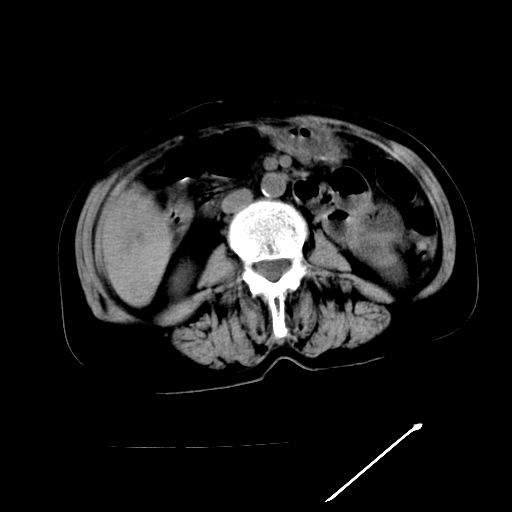

以下是引用随光逐影在2009-4-7 8:21:00的发言:[br]肝内外胆管多发性结石并肝内外胆管扩张;胆系感染。